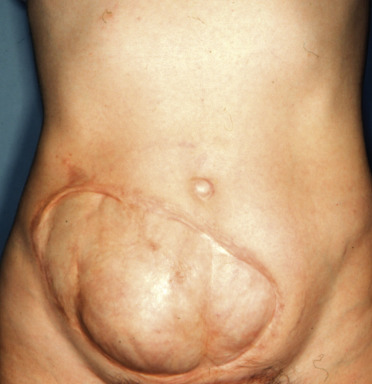

A 41-year-old woman with a full-thickness abdominal wall defect measuring 25 × 14 cm, 12 years after radical resection of a dermatofibrosarcoma protuberans and reconstruction with skin graft.